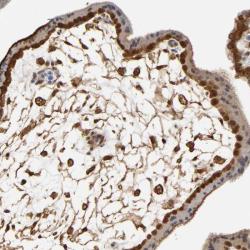

Supportive validation

- Experimental details

- Immunohistochemical staining of human placenta shows strong cytoplasmic positivity in trophoblastic cells.

- Validation comment

- Staining pattern consistent with experimental and/or bioinformatic data.